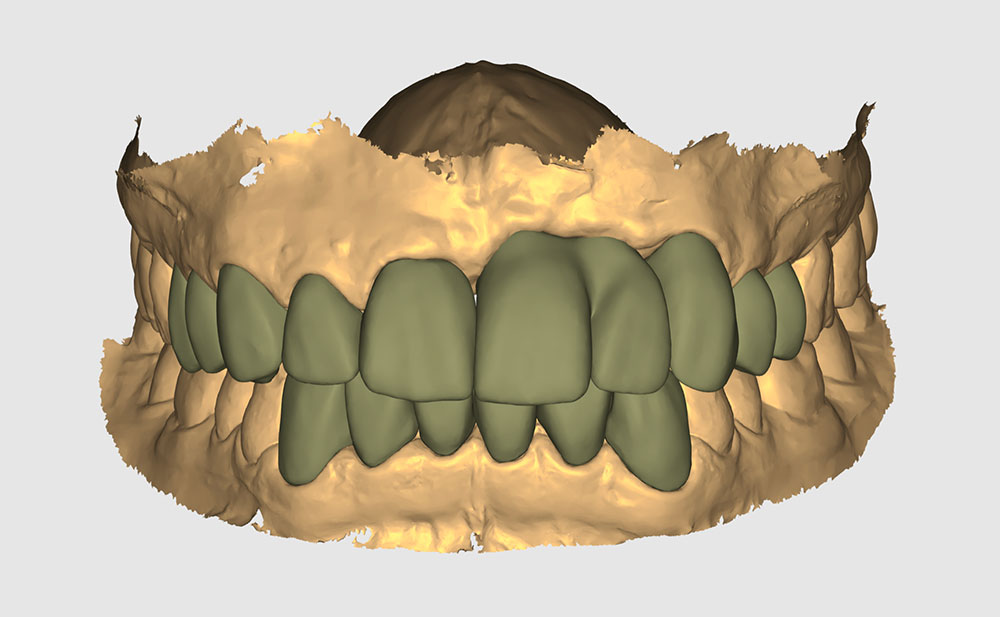

Planificación

Planificación